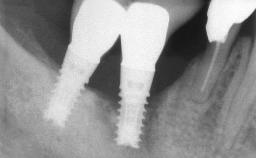

Peri-implant Carcinoma

Oral implants are highly successful and offer long-term benefits, especially in the rehabilitation of edentulous patients or patients with oral defects following ablative tumor surgery (Albrektsson and coworkers 1986), and also after radiation therapy (Schiegnitz and coworkers 2014). With the number of implants placed globally going into the millions, implant dentists have observed some rare adverse events. Although carcinogenesis around implants is an exceedingly rare phenomenon, we recently reported about 15 patients treated for carcinomas adjacent to implants at our clinical department over a period of fifteen years (Moergel and coworkers 2014). The following case represents a patient of this cohort; it discusses possible risk factors and makes suggestions for a recall schedule. A 70-year-old woman was referred to our outpatient department for evaluation of a rapidly growing macroscopic alteration of the mucosa in the left mandible.